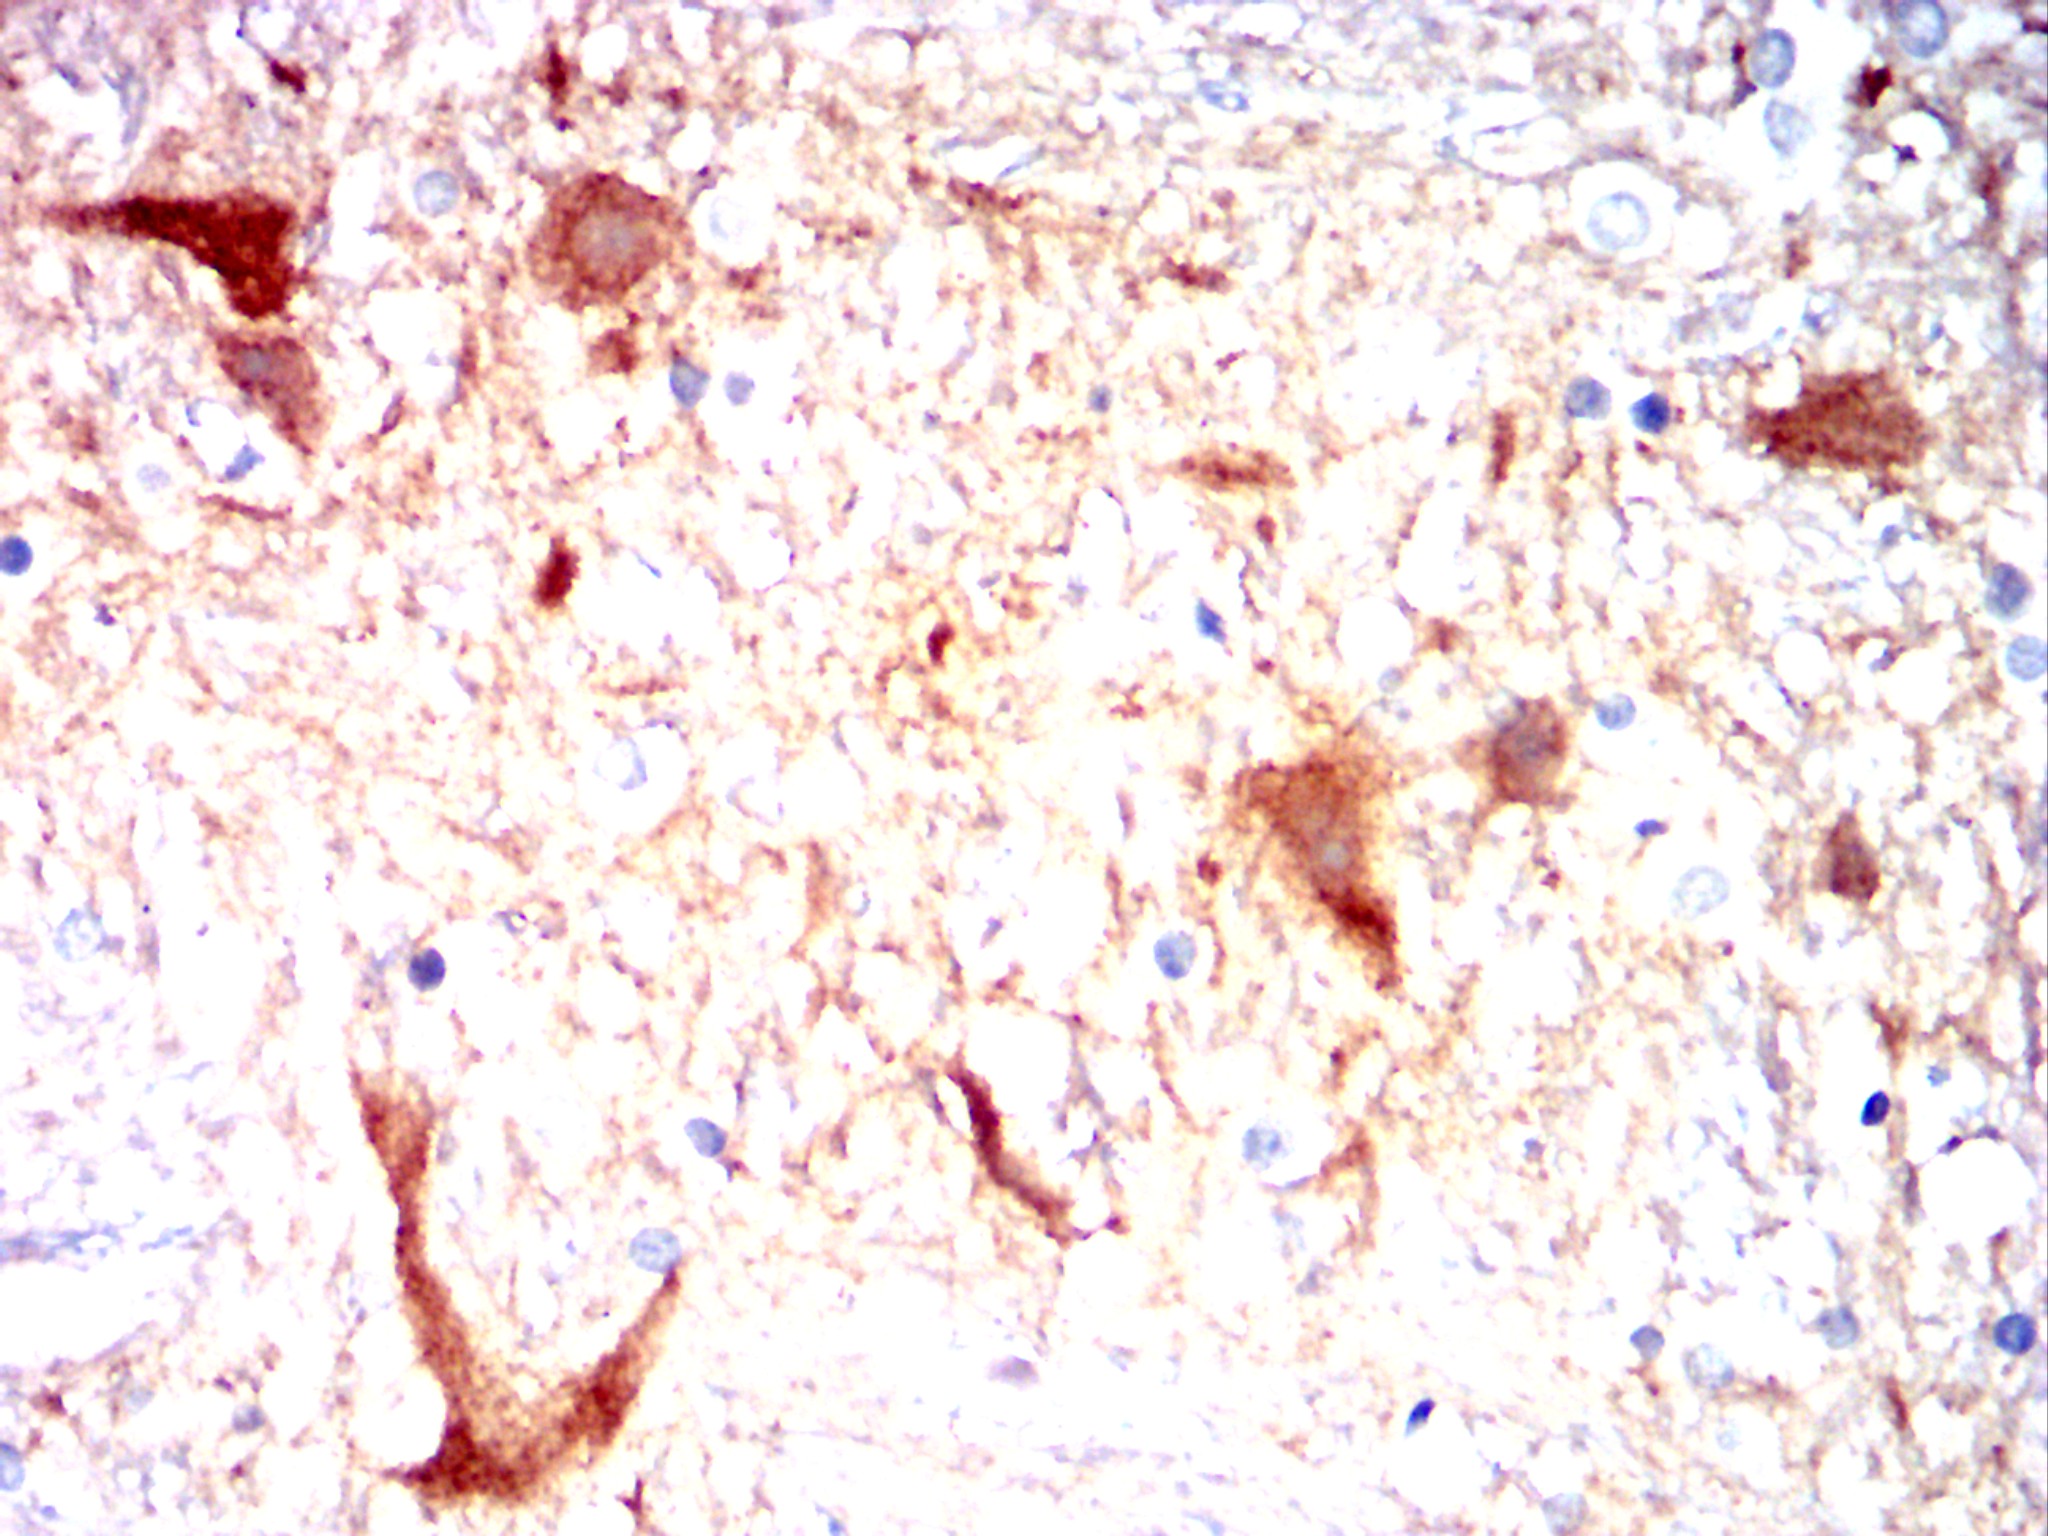

Immunohistochemical analysis of paraffin-embedded Rabbit spinal cord using CAMK2G mouse mAb with DAB staining.